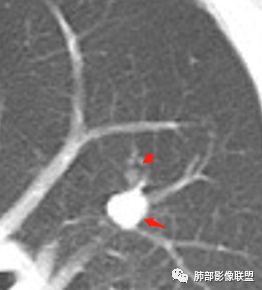

几个结节

下面这一支堵了

前后对比,这些结节其实是没引起支气管远端病变的

南大标注,这几个确实结节没有阻塞支气管,感觉是在血管分叉地方。

@南边 关键是上面这几个结节有的密度度,有的密度低。与下面堵塞支气管的结节样改变是否不是一回事,

后头看前片似乎当时腔内壁稍增厚一点

常规腔内病灶引起远端炎症:

1、肿瘤,良性、恶性?短时间出来——恶性

2、炎性,结核、真菌多见,但是表面膨隆、光滑,不太支持,放待排

3、异物、痰栓,附近的结节不支持,最好有密度测量、强化情况

就目前的资料:我支持恶性肿瘤,待排异物

常规下一步:支气管镜、增强扫描

@南边 我觉得最关键的是两个问题,一是腔内堵塞这个结节的纵隔窗看不到,所以到底是不是结节样肿物不明确,第二个就是没有增强,这个腔内病变与周围结节的强化性质是否一致,强化程度及强化曲线如何?

我们需要做的:我认为最主要是发现支气管腔内病灶